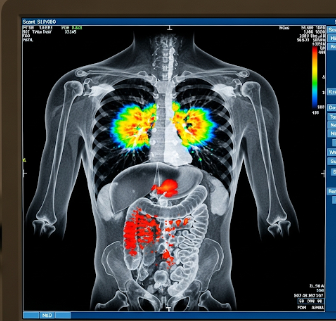

PET (Positron Emission Tomography) scan is an advanced imaging technique that helps visualize metabolic activity in tissues and organs. It is widely used for cancer detection, monitoring treatment response, evaluating heart disease, and detecting brain disorders.

A PET scan uses radioactive tracers to measure metabolic activity in cells. Key features include:

✔ Functional imaging: Unlike CT or MRI, PET shows how tissues function rather than just their structure.

➔ Tracer-based technique: A small amount of radioactive material (e.g., FDG) is injected into the body.

● High sensitivity: Detects early disease changes before structural abnormalities appear.

★ Combination imaging: Often combined with CT or MRI for detailed anatomical mapping.

PET scans are particularly useful for cancer staging, detecting recurrence, assessing heart perfusion, and evaluating brain disorders such as Alzheimer’s disease.